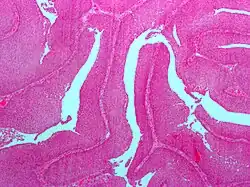

| Micrograph of a PUNLMP. Intermediate magnification. H&E stain. | |

Papillary urothelial neoplasm of low malignant potential (PUNLMP) is an exophytic (outward growing), (microscopically) nipple-shaped (or papillary) pre-malignant growth of the lining of the upper genitourinary tract (the urothelium), which includes the renal pelvis, ureters, urinary bladder and part of the urethra.

Histologically, they have a papillary architecture with slender fibro vascular cores and rare basal mitoses. The papillae rarely fuse and uncommonly branch. Cytologically, they have uniform nuclear enlargement.